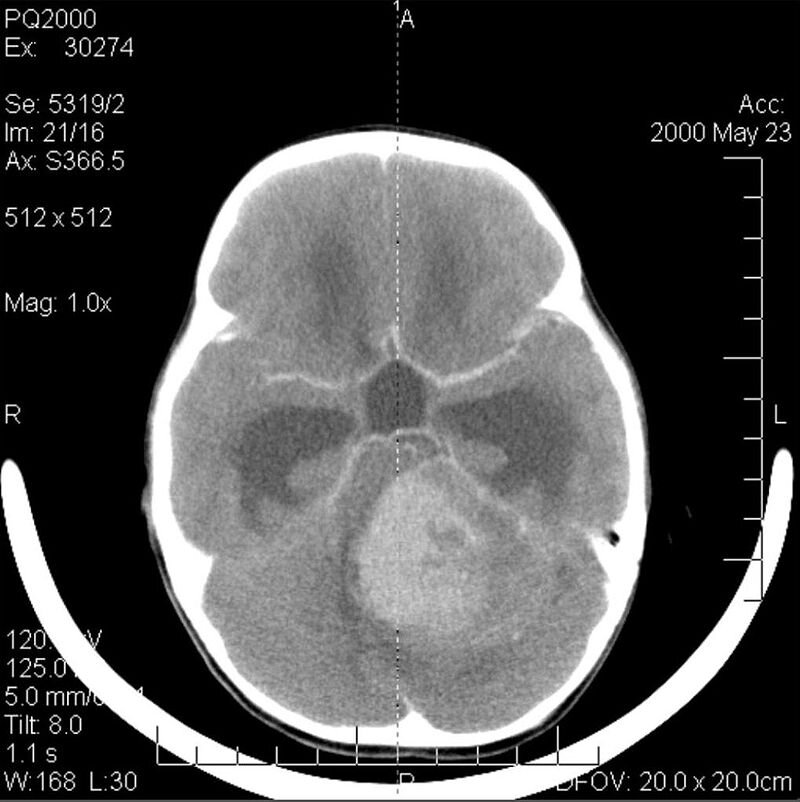

В испытание вошли 43 пациента с гистопатологически подтверждённым типом опухоли. Перед тем, как вводить препарат, врачи оценивали адекватность тока спинномозговой жидкости с помощью небольших доз 124I-3F8 или 131I-3F8 и их дальнейшей визуализации. Таким образом, индивидуально рассчитались дозовые нагрузки, а затем, если всё было хорошо, каждому больному вводилось до четырёх терапевтических инъекций 131I-3F8 (всего ввели 167 доз). Эффективность лечения учёные оценивали, сравнивая МР-снимки до и после терапии примерно через каждые 3 месяца в течение первого года после инъекций, а потом МРТ проводили через каждые 6-12 месяцев.

Общая поглощённая доза составила 1453 сГр, а медиана выживаемости после первой дозы оказалась равной 24,9 месяца. Причём, у всех пациентов зафиксировали стойкую ремиссию как на основе МР-данных, так и цитологически, то есть на два года клинического испытания рост опухоли полностью подавился. Соотвественно, эти люди имели и значительно более низкий риск смерти по сравнению с теми пациентами, кто лечение не получал.